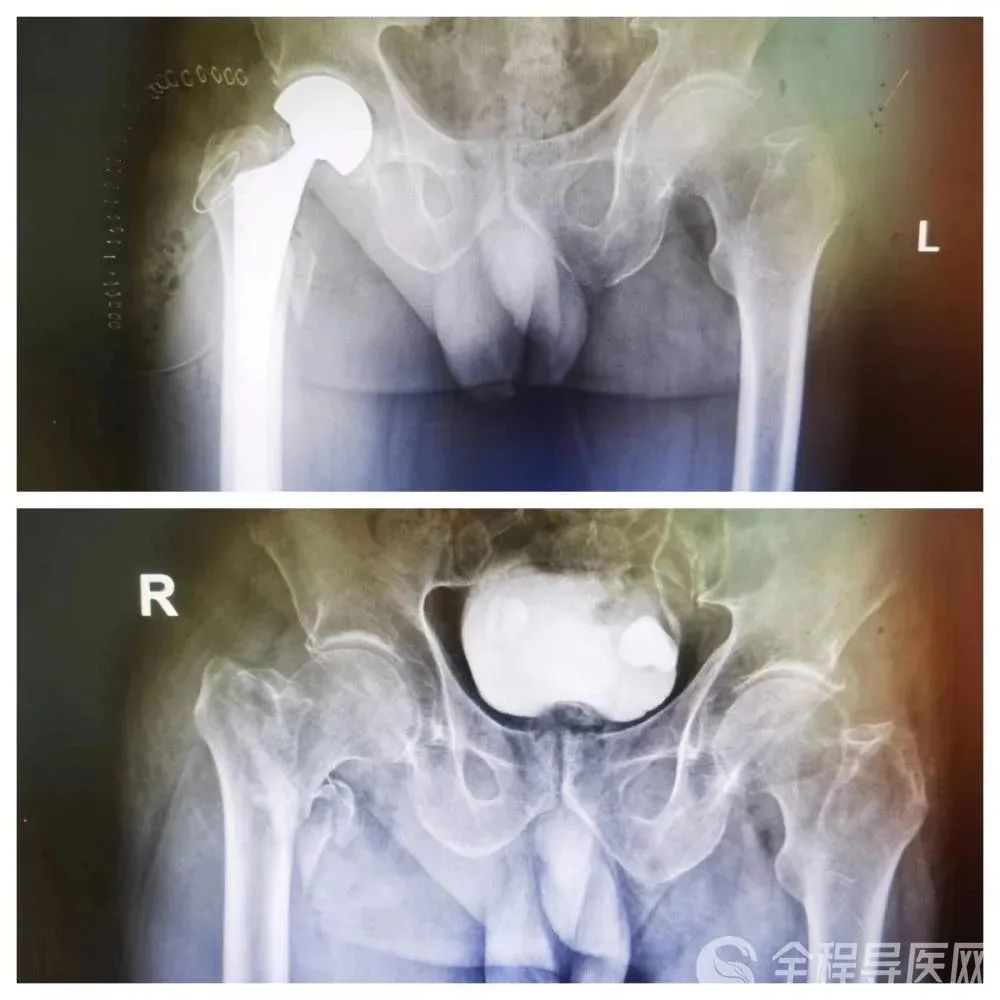

入院后,张奶奶被诊断为股骨粗隆间骨折。徐州矿务集团总医院骨-关节外科周雷主任介绍,髋关节骨折也常被人称之为“人生最后一次骨折”,之所以这么形容,主要是在于其死亡率和致残率非常高,致残率高就意味着病人要躺在床上或坐在轮椅上,生活质量极低,对家庭和社会的危害很大。

这道“风险题” 骨科满分

周雷主任表示,髋关节骨折的治疗方案有两种,一种是保守治疗,拉牵引治疗。这种治疗一般需要卧床三个月,且由于老年人骨质疏松,骨质较差,其骨折断端是否能够成功愈合未知。第二种是手术治疗,人工股骨头置换术。这种手术采用微创小切口的方式,术后恢复快,还能够快速止痛。在手术及护理后,三天内就可以下地活动,避免了长期卧床引发并发症。

术前,骨科手术团队集合MDT团队进行了充分沟通,对术中可能出现的问题进行预判,并商讨完善的手术方案。最终,骨科团队成功为张奶奶完成了“人工股骨头置换术”。